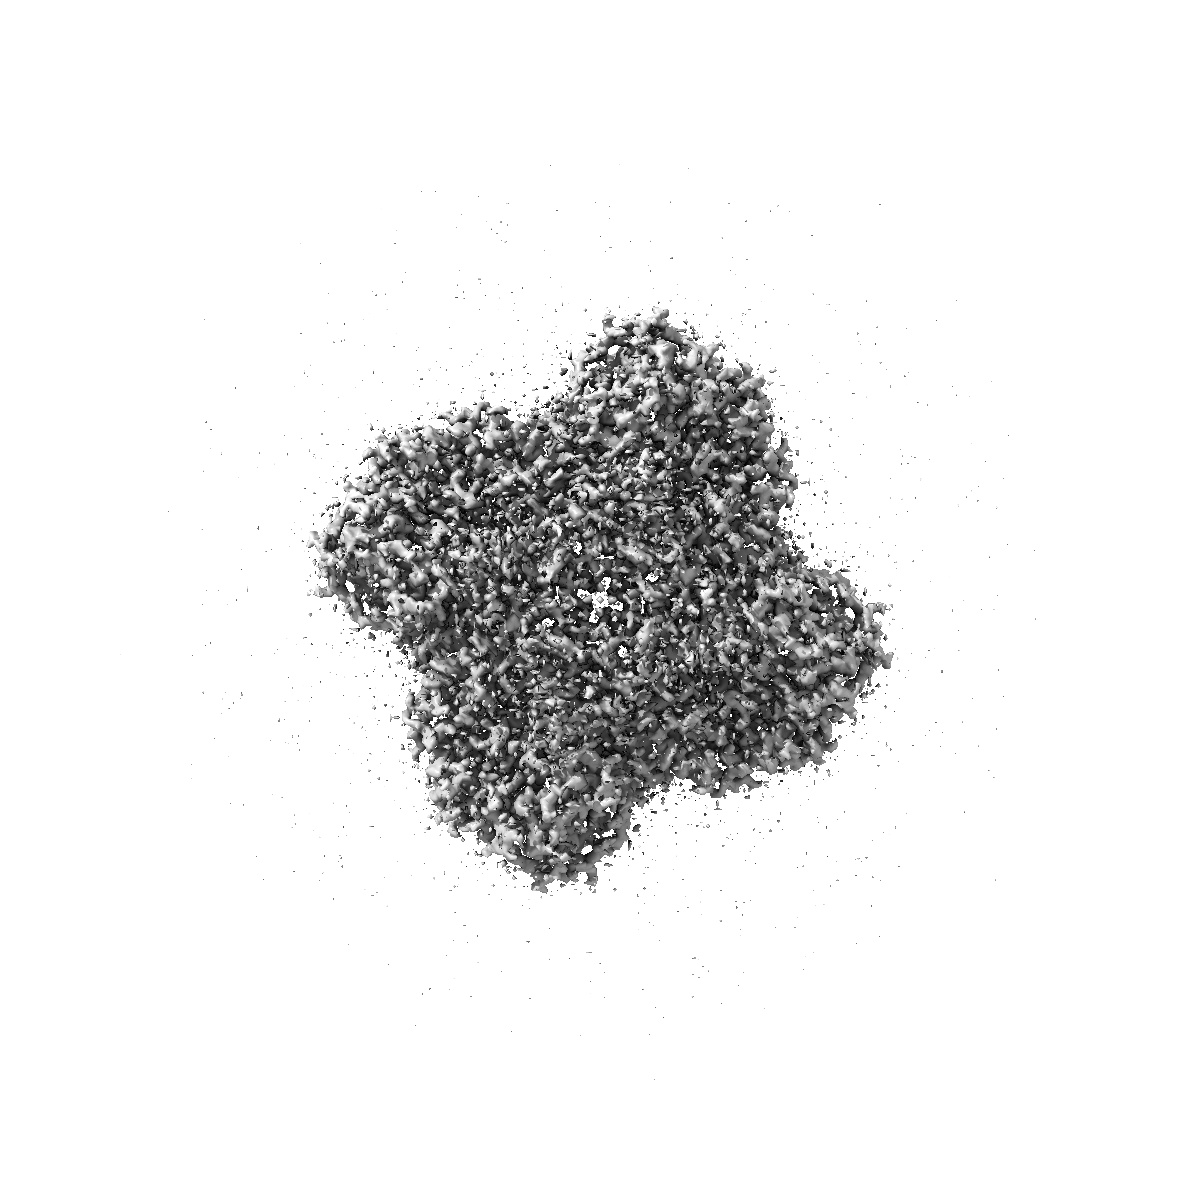

EMD-52255

Influenza Neuraminidase in complex with N-Acyl Oseltamivir inhibitor

Sample Organism: Influenza A virus

Sample: Influenza Neuraminidase in complex with N-Acyl Oseltamivir inhibitor

Fitted models: 9hli

Deposition Authors: Moran E, Davies G

Oseltamivir aziridines are potent influenza neuraminidase inhibitors and imaging agents.